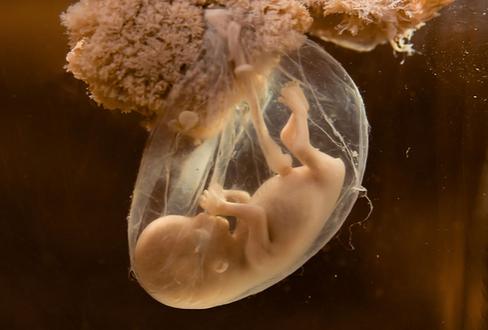

在胎儿的不同发育阶段,羊水的来源也各不相同。在妊娠第一个三月期,羊水主要来自胚胎的血浆成分,之后,随着胚胎的器官开始成熟发育,其他诸如胎儿的尿液、呼吸系统、胃肠道、脐带、胎盘表面等等,也都成为了羊水的来源。所以羊水的多少不但和母亲有关,也和胎儿的发育有很大关系。